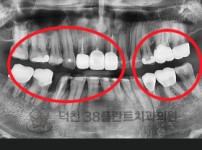

치료전후